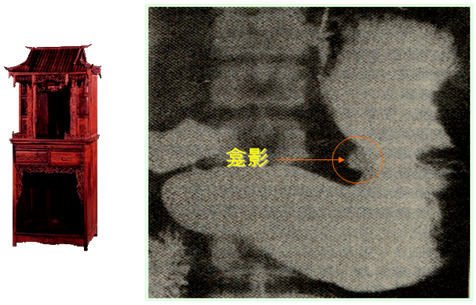

X线钡餐 | 龛影——直接确诊价值;十二指肠球部激惹和球部变形、胃大弯侧痉挛切——间接征象 | |